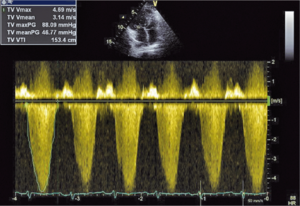

Głównym mechanizmem patogenetycznym twardziny układowej jest zwiększona produkcja aminopropeptydu kolagenu typu III, w następstwie czego dochodzi do włóknienia tkanek (ryc. 1). Zwiększenie sztywności naczyń koreluje z zaawansowaniem choroby [3-5] i może prowadzić do ciężkiego powikłania, jakim jest tętnicze nadciśnienie płucne (ryc. 2, 3) [6].